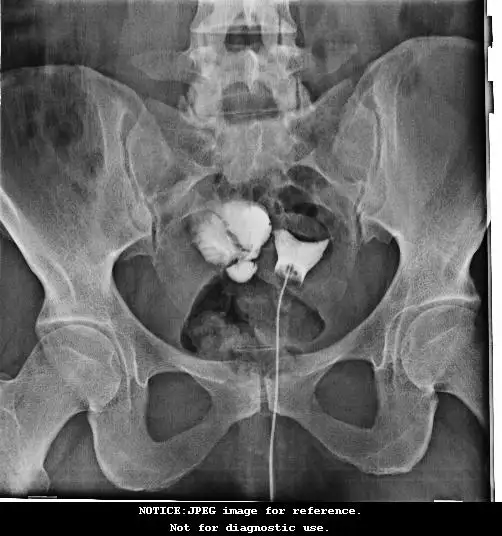

Ben 28 yasında 4 aylık evliyim.2007 yılında sol over kıstten amelıyat olup sol yumurtalıgım alındı.Ocak 2015 ayında dıs gebelık gecırdım.Subat ayında adetımden sonra Hgs fılmı cektırmıstım. Fim sonucunda sol tupum kapalı sag tupde de hısrosalpınks oldugunu ogrendım. Ultrason muayenesınde de Yumurta rezervemın dustugunu ogrendım ve bıosteron ılacını kullanıyorum gunde 3 defa. Bana soylenılen ılk asamada laporoskopı amelıyatı olup sağ tupu alıp tup bebek tedavısıne baslamaktı.Tupun ıcerısındekı sıvının tup bebek olusumuna zarar verecegı soylenmıstı.hocam tereddutte kaldıgım konuyu ıleteyım. Bu rahatsızlıgımda dolayı bır cok hastaneye ve doktora muayene oldum.

Hocam lutfen yardım edın . ne yapabılırım. Kafam cok karıstı. Yanlıs bır ışlem yapmak ıstemıyorum. fim sonucunu ıletıyorum.

1-Öncelikle tüplerinizi aldırınız.Kapalı olanı da aldırınız(Filmde spazma bağlı görülmemiş olabilir)Ne olur ne olmaz.Tüp ameliyatından bir ay sonraki ilk adetinizle tüp bebek tedavisi yapılabilir.